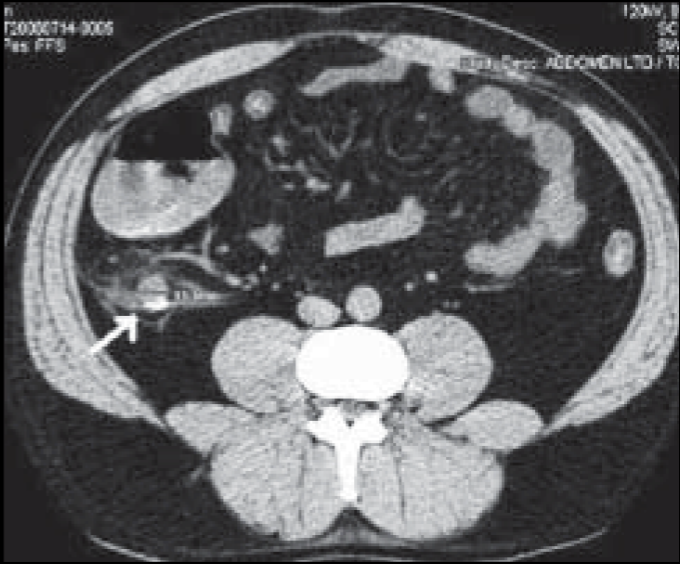

13

Q

Grasa sucia

Apendicolito

Realce con contraste

Lo MEJOR

A

TC

14

Apendicitis